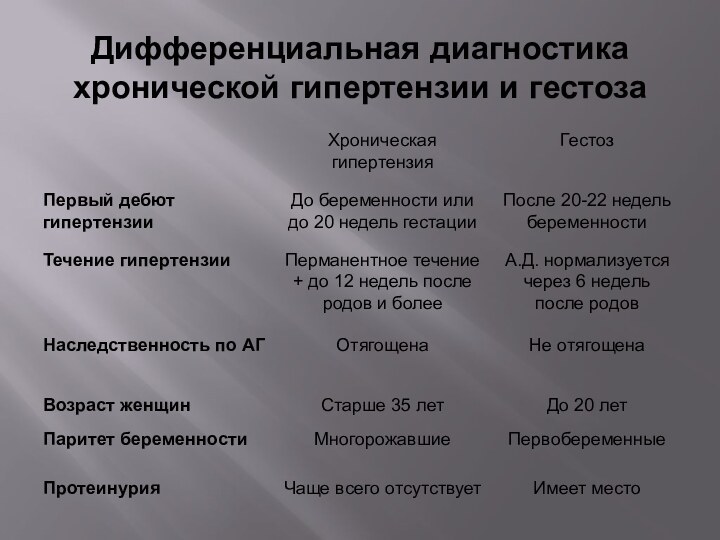

Дифференциальная диагностика заболеваний плевры